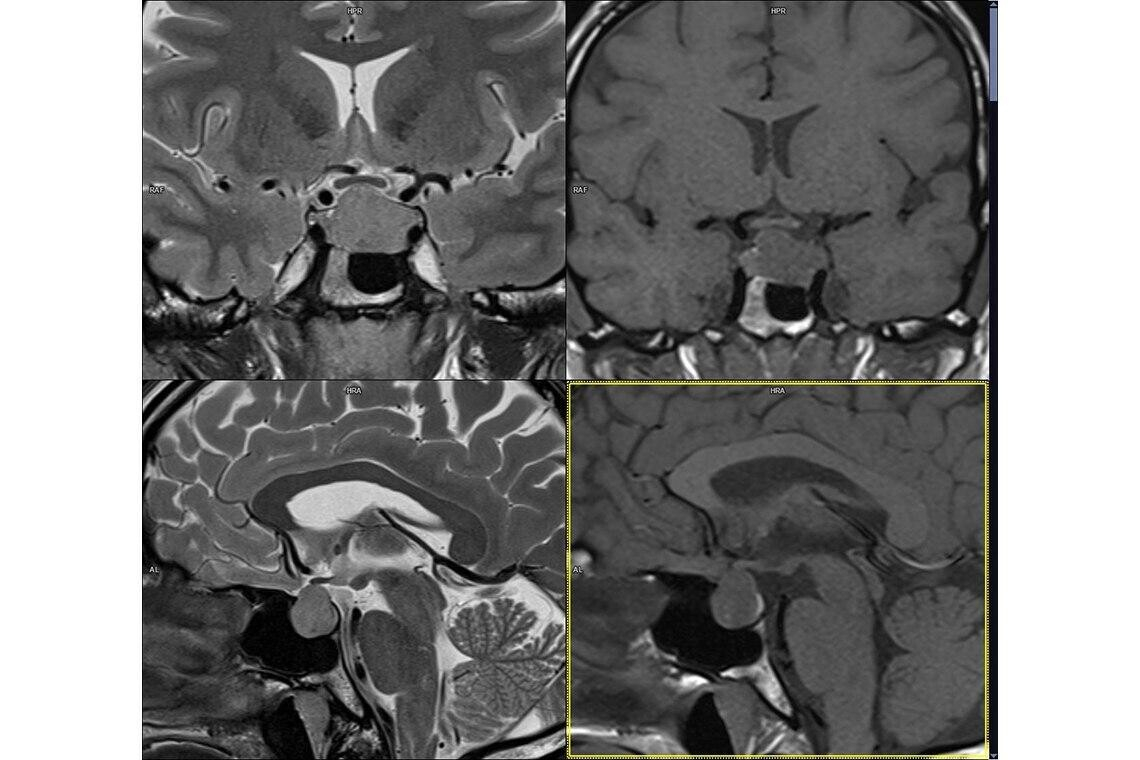

Подтверждением диагноза являются:

- МРТ головного мозга и гипофиза;

Самым информативным способом для выявления опухолей является МРТ. А вот прогноз по восстановлению фертильности в таких случаях различный.